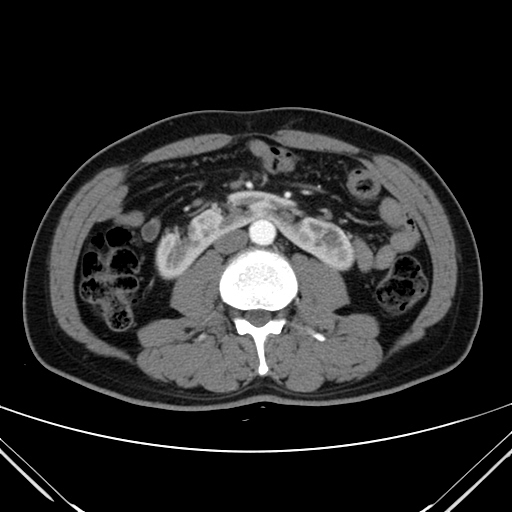

»çÁøCT/MRI